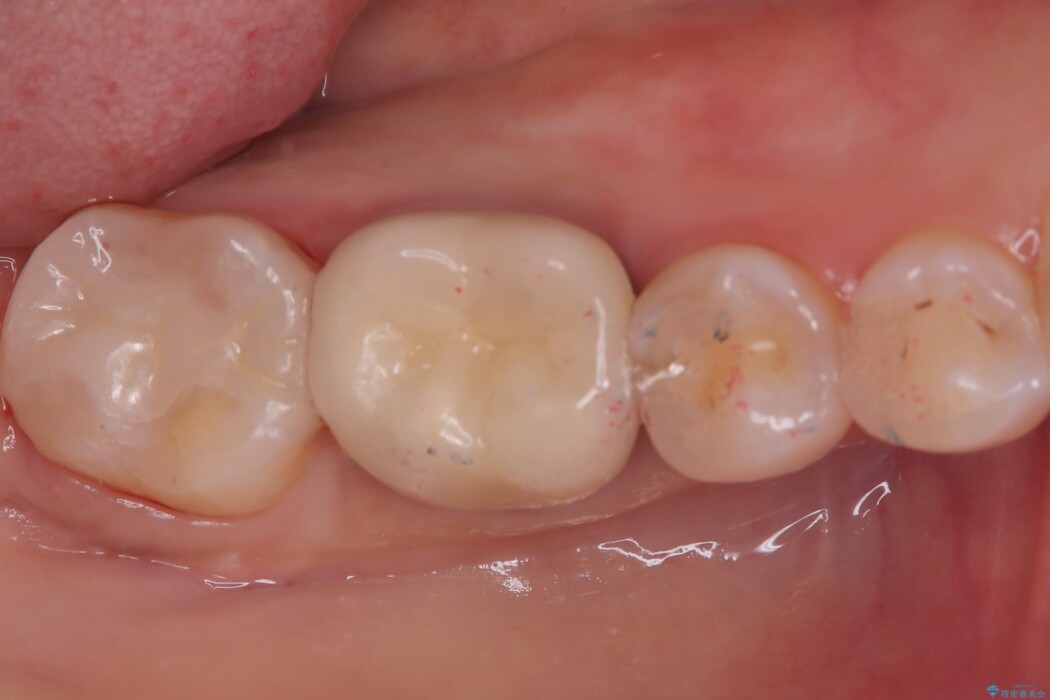

右下奥歯の広範囲な虫歯と劣化した古い詰め物をすべて除去し、新しくセラミックインレーで修復しました。装着時にはラバーダムを使用し、湿気を遮断した状態で精密に接着させています。